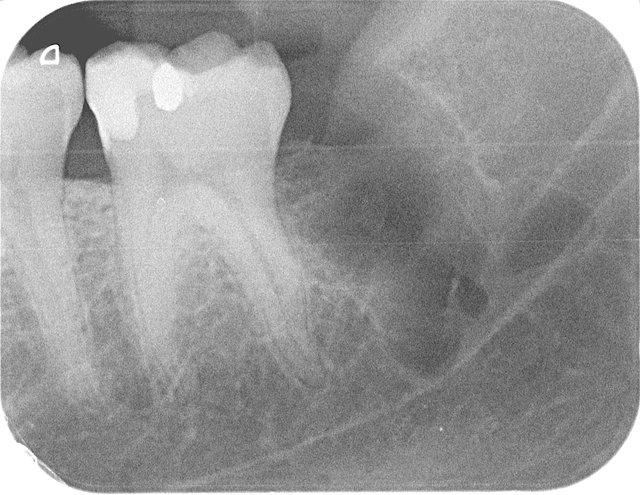

Tiefe Karies wegen eines benachbarten Weisheitszahnes

Tiefe Karies wegen eines benachbarten Weisheitszahnes ...

Composit-Füllung by CLINICDENT ✓